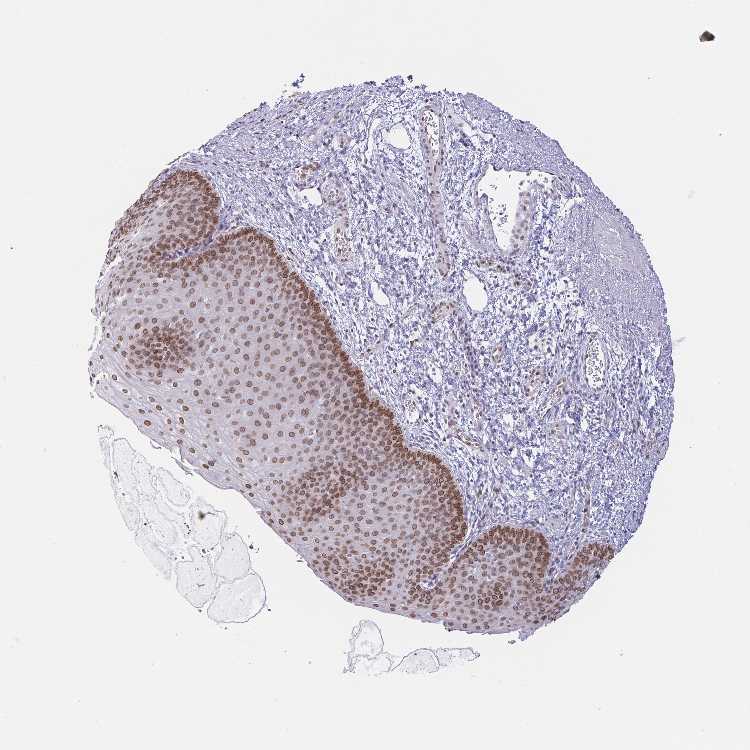

ESOPHAGUS - Antibody stainingi

Antibody staining in the annotated cell types in the current human tissue is reported as not detected, low, medium, or high, based on conventional immunohistochemistry profiling in selected tissues. This score is based on the combination of the staining intensity and fraction of stained cells.

Each image is clickable and will lead to virtual microscopy that enables deeper exploration of all samples and also displays staining intensity scores, fraction scores and subcellular localization as well as patient and tissue information for each sample.

Antibody HPA003435Antibody HPA050204

Squamous epithelial cells MediumHigh